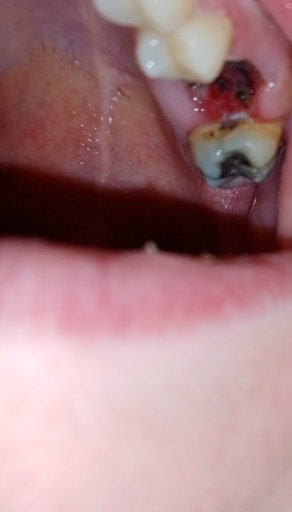

Is this tooth extraction healing correctly?

I still have minor pain. It was a root canal with a screw. I never went back to finish it. Now the tooth is dead. I am taking antibiotics and ibuprofen for the pain. It's been five days and I've also done salt rinses. I'm not certain, thank you...